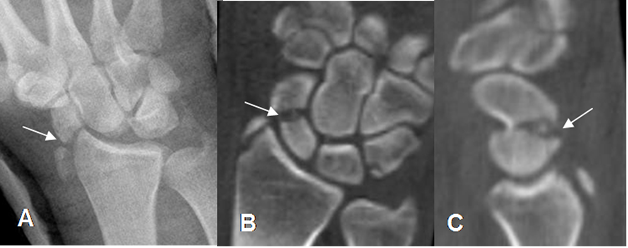

Fig 42. Fractura del piramidal.

A: Rx lateral. Fragmento óseo suelto en la parte posterior del tercio medio del carpo, por fractura del piramidal.

B: TAC axial y C: TAC reconstrucción sagital. Fractura del piramidal.

Fig 43. Fractura del piramidal.

A: RM coronal en T1 y B: RM coronal en STIR. Edema óseo del piramidal, con fractura no desplazada, en sentido oblicuo.